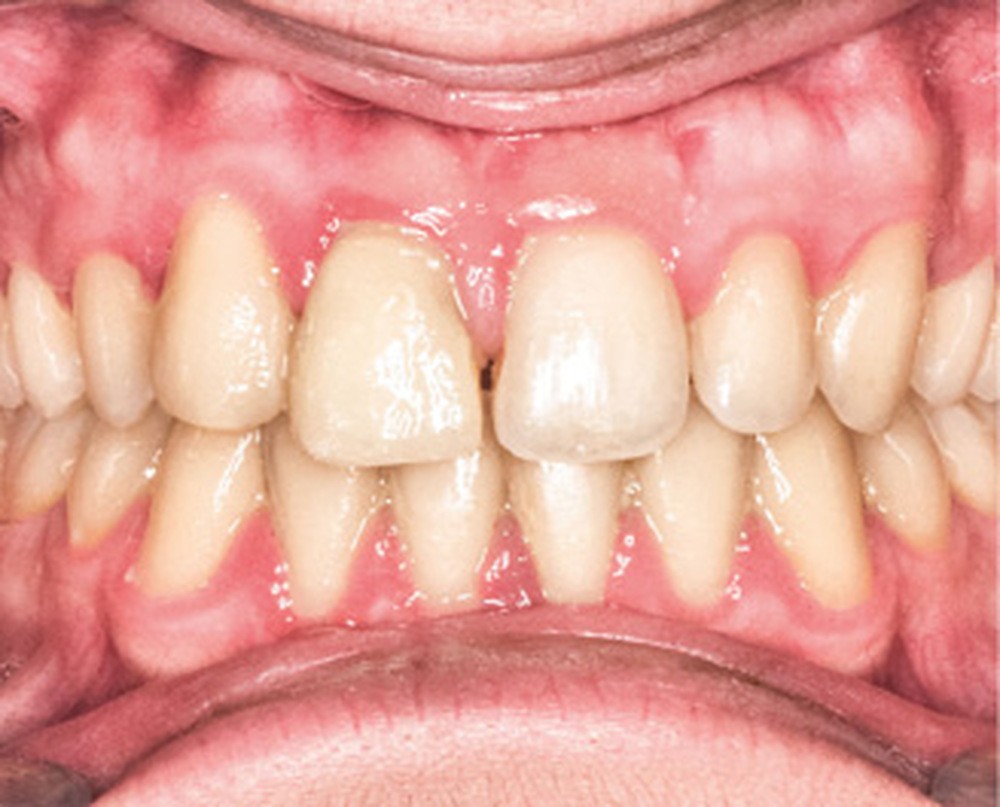

D’un point de vue occlusal, le patient, en denture adulte jeune stable, présente une classe II d’Angle bilatérale de 4 mm, associée à un encombrement maxillaire de 5 mm et mandibulaire de 2 mm. La face mésiale de 21 est centrée avec le plan sagittal médian, la non-concordance des médianes incisives est d’origine mandibulaire (déviation de la médiane mandibulaire vers la gauche) (fig. 1b-d).

En ce qui concerne les objectifs de traitement, le profil du patient reste pratiquement inchangé avec une compétence labiale au repos (fig. 4a). D’un point de vue occlusal, la correction en classe I d’Angle est obtenue (fig. 4b-c). La difficulté résidait dans la gestion de la substitution (fig. 5) ; outre le manque d’hygiène notable due à une perte de motivation du patient sur la fin de traitement, notons une perte d’alignement de la ligne des collets en regard de 13, ainsi qu’une bosse canine toujours présente. Une correction par chirurgie parodontale permettra la symétrie du sourire et l’intégration prothétique optimale de la restauration de 11 [3] (fig. 6).